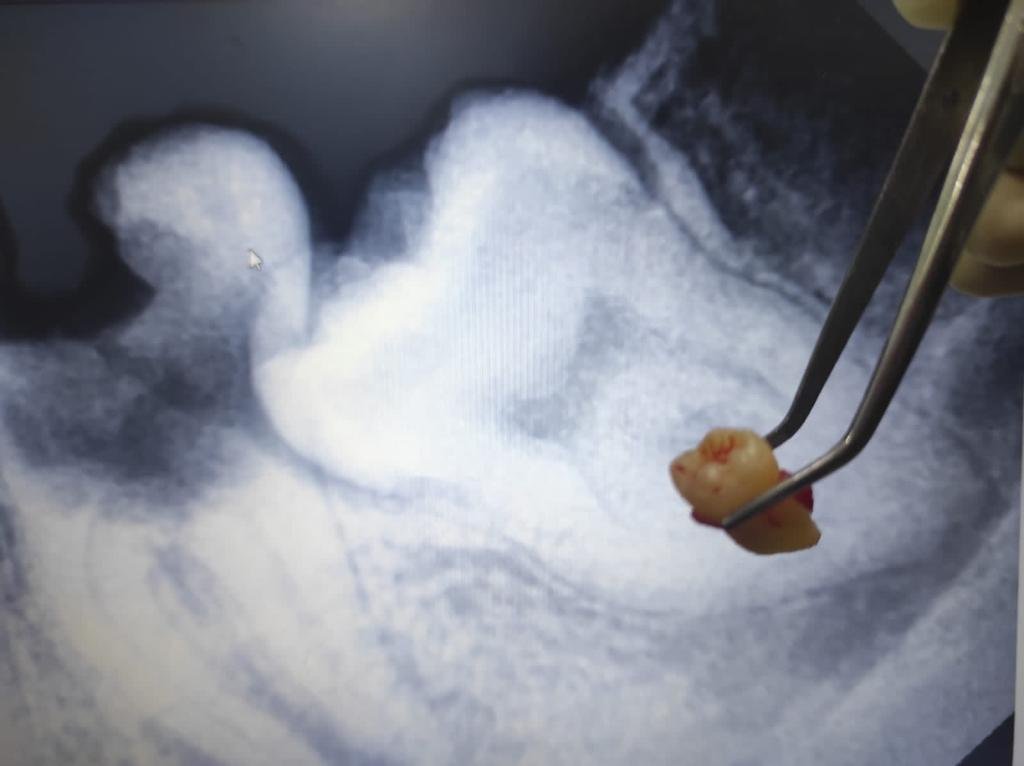

Bila gigi sulit dicabut, dokter membaginya menjadi beberapa bagian lalu mengangkat potongan satu per satu.

After dari Cabut Gigi Bungsu